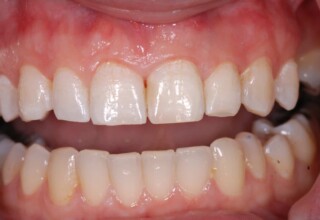

Whitening of non-vital teeth

Teeth with a root canal often lose their brightness and darken to an unesthetic level. Their bleaching requires an excellent root canal and patience. An adhesive filling is placed inside the root to confine the bleaching effect to the tooth part which is visible in the oral cavity. The actual bleaching may require 1-5 short sessions for the placement and renewal of the bleaching material. After the bleaching a high quality adhesive filling is mandatory.

Initial appearance

Final appearance